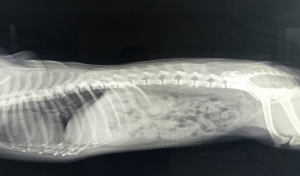

Canine Physical Program Common Sickness in Sport Dogs

I have chosen to write about some of the most common health problems with our sport dogs.

In this course, you …

Canine Physical Program Rehabilitate Injuries

This course is about how you can rehabilitate your injured dog at home and how you can check your dog by yourself if …